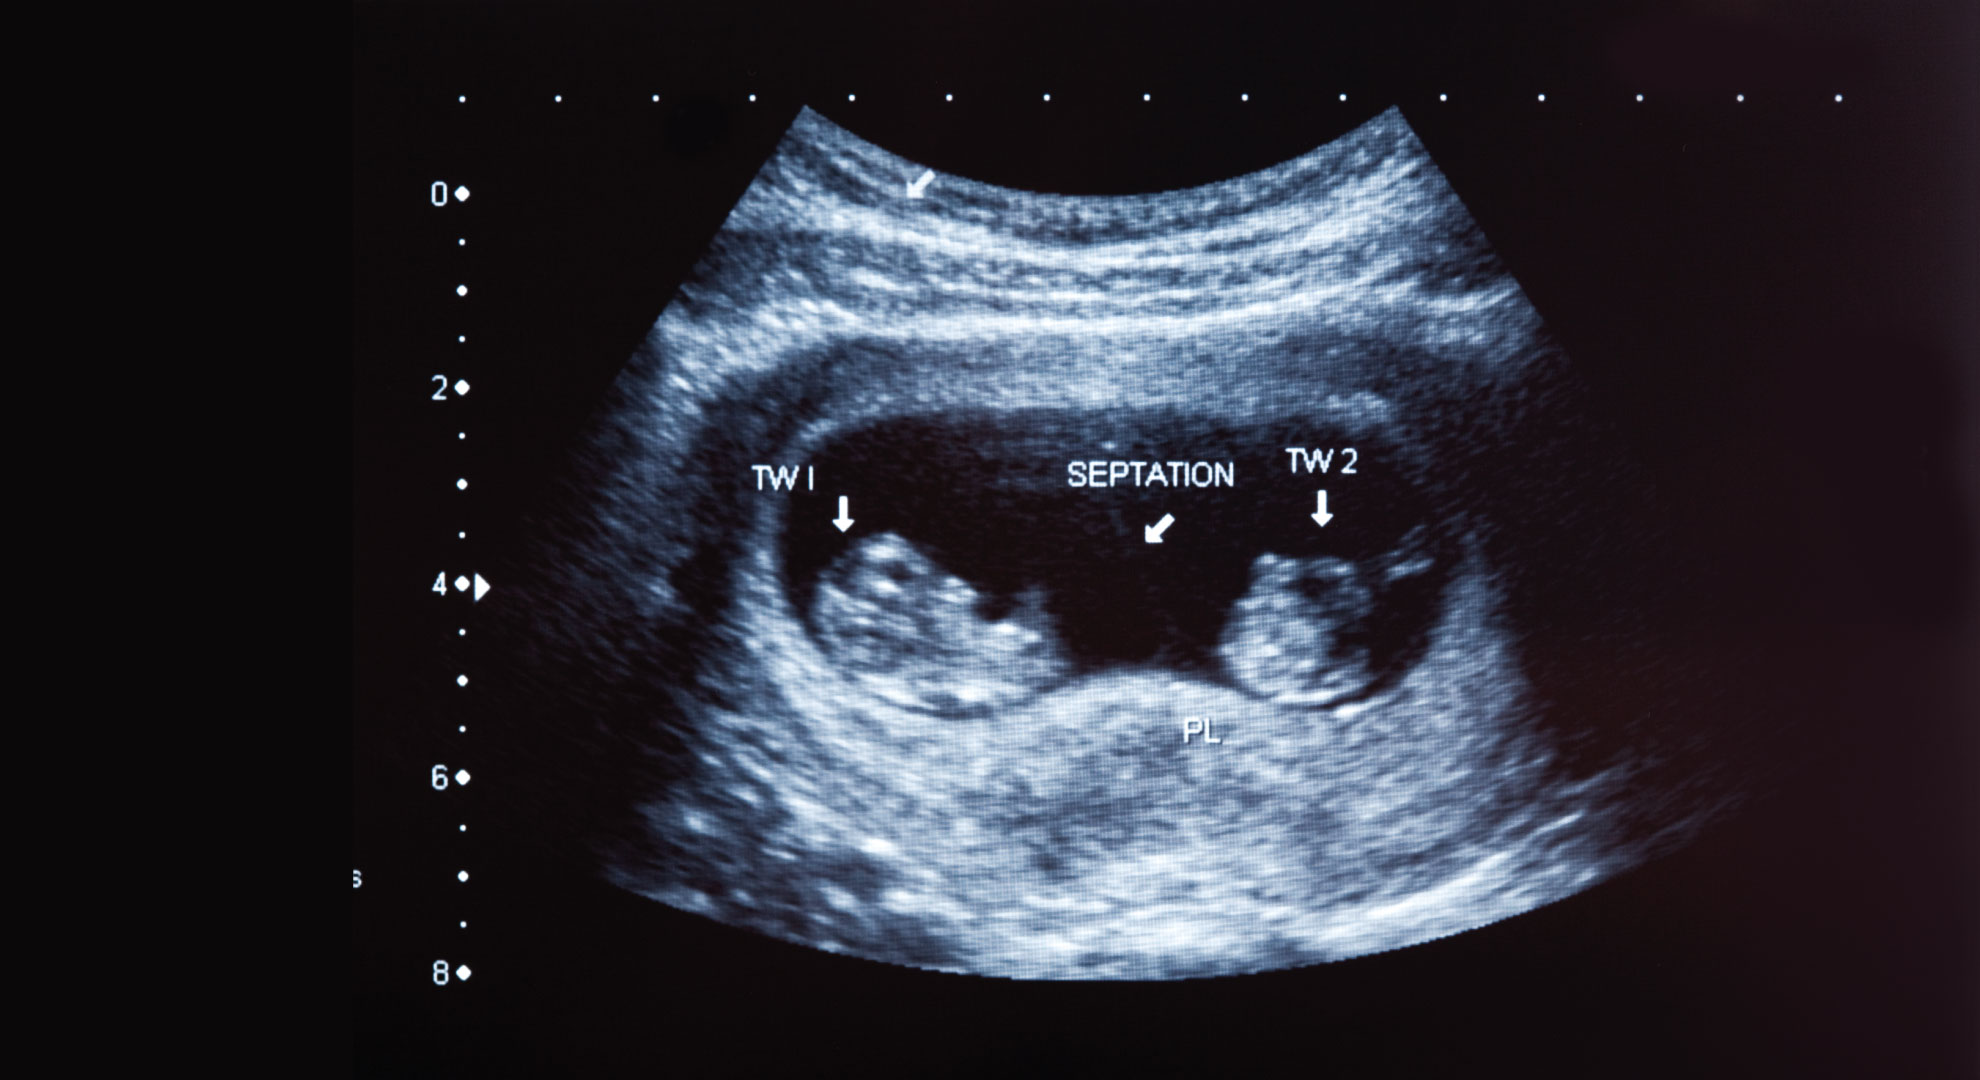

Вагітність стає багатоплідною, коли одночасно запліднюються кілька яйцеклітин або коли один ембріон, утворений яйцеклітиною та сперматозоїдом, поділяється на кілька ембріонів. У першому випадку близнюки різнозиготні, або різнояйцеві. Вони не ідентичні генетично, тому можуть бути одностатевими або різностатевими, їх зовнішність різна. У другому випадку близнюки однояйцеві, або монозиготні. Генетично вони ідентичні, тому завжди однієї статі та схожої зовнішності.

Залежно від стадії, на якій розділився ембріон, в однояйцевих близнюків може бути загальна плацента та гестаційний мішок, а можуть бути різні плаценти та окремі гестаційні мішки. У поодиноких випадках однояйцеві близнюки перебувають в одному амніотичному мішку.